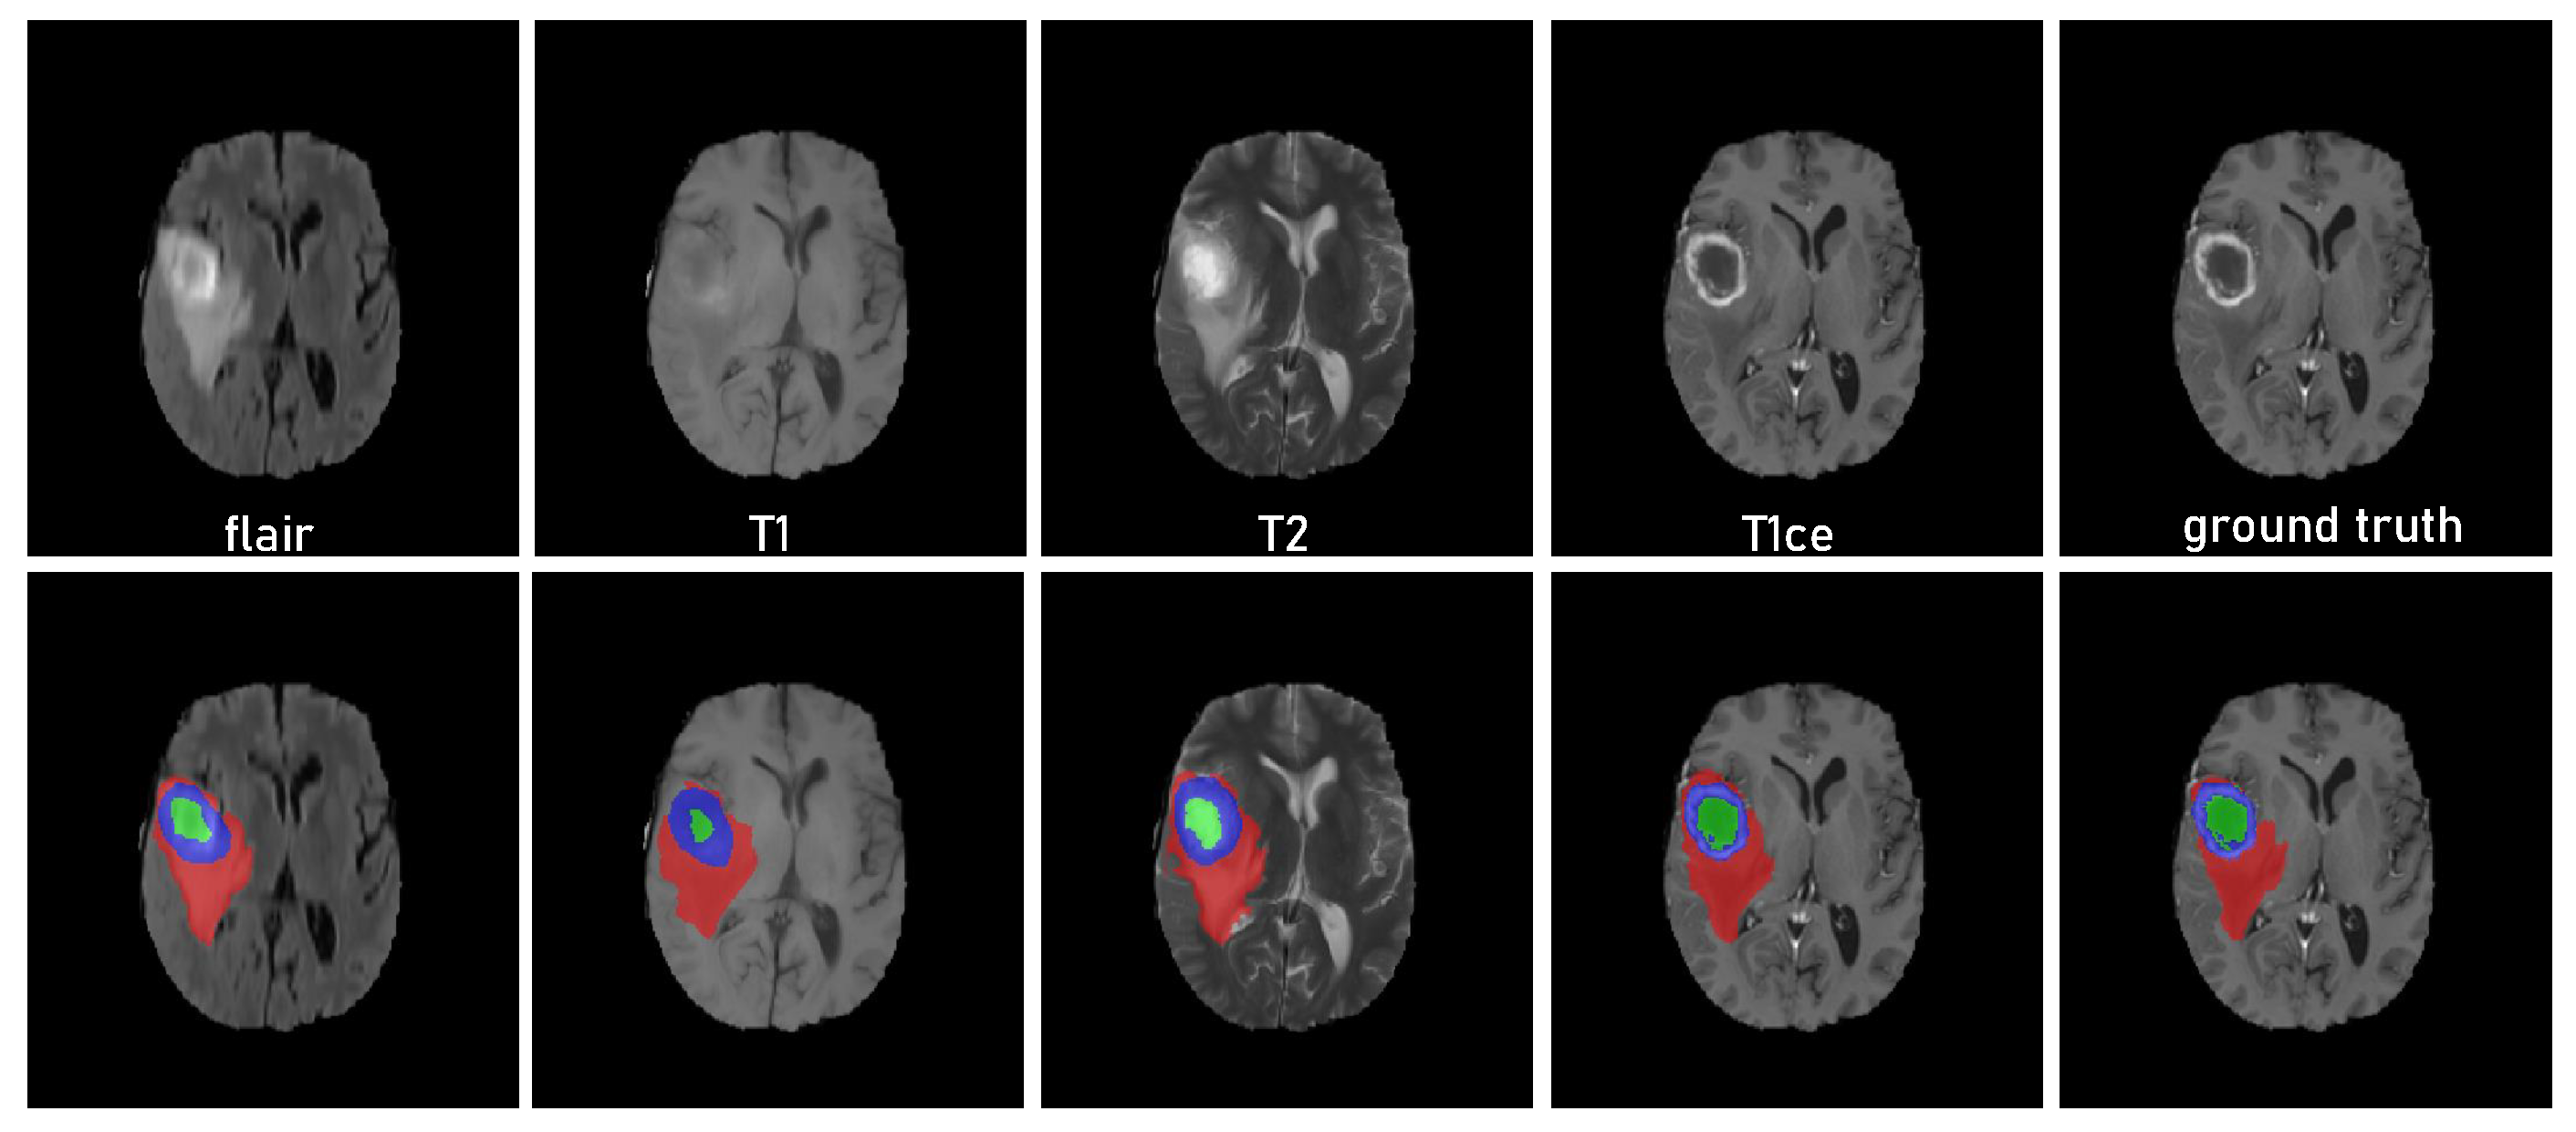

3.1. Dataset